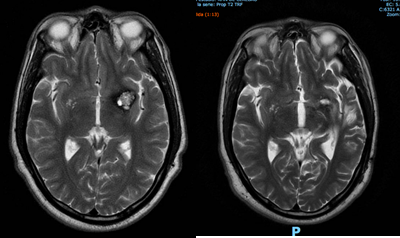

Cuando los cavernomas incidentales están localizados en zonas periventrículares con componente exofítico intraventricular, el riesgo de hemorragia ventricular y la accesibilidad a la lesión sin transgredir tejido sano inclinan la balanza hacia el tratamiento microquirúrgico.

Otra de las localizaciones en que se evalúa cirugía aunque sean cavernomas incidentales es en áreas potencialmente epileptógenas (por ej. témporo mesial), sobre todo si tienen un importante halo de hemosiderina (en T2). Es conocida la posibilidad de refractariedad de las crisis de estas lesiones cuando se vuelven sintomáticas.

La última localización a evaluar son los cavernomas incidentales de fosa posterior, sobre todo cerebelosos, hemisféricos o paravermianos, y accesibles, ya que estas lesiones en nuestra experiencia tienen más propensión, cuando sangran, a formar hematomas de mayor tamaño que los supratentoriales, por lo que se propone y analiza la cirugía con el paciente.